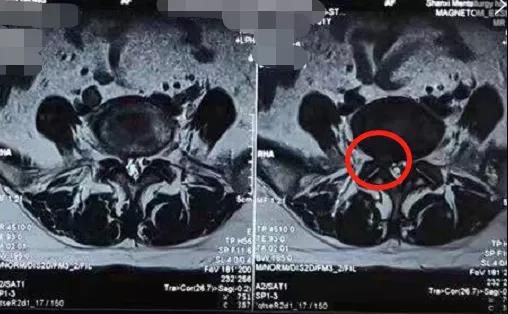

熊东主任接诊后,结合赵女士的查体及其他各项检查结果,确诊患者为“腰椎间盘突出症(腰5骶1)”。从患者的影像学资料可以看到,在腰5骶1处已经出现比较严重的突出并且压迫到神经,患者的症状明显,这种情况建议进行椎间孔镜手术微创治疗。

术前影像学资料: